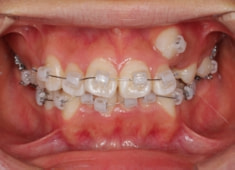

治療前

治療後(2年後)